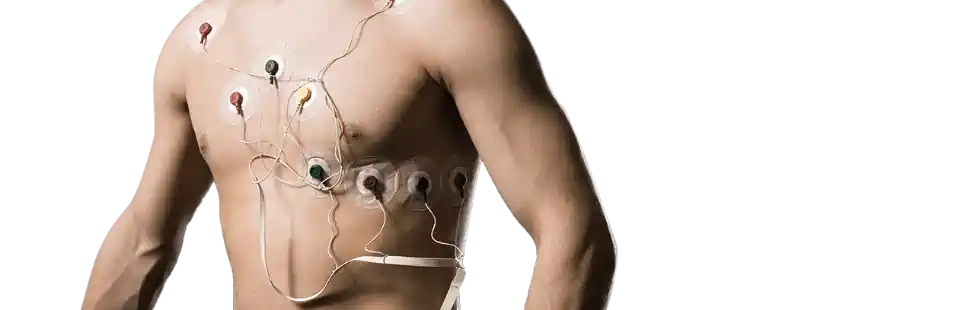

ECG הולטר לב

הולטר לב - המדריך עם כל המידע הרפואי והמעודכן הולטר לב - ECG היא בדיקה המשמשת לניטור פעילות חשמלית בלב ברציפות למשך 24, 48 ולעיתים אפילו 72 שעות. ליבנו פועם ללא הפסקה לאורך כל ימי חיינו. קצב הפעימות משתנה בהתאם לפעילות שאנו מבצעים (